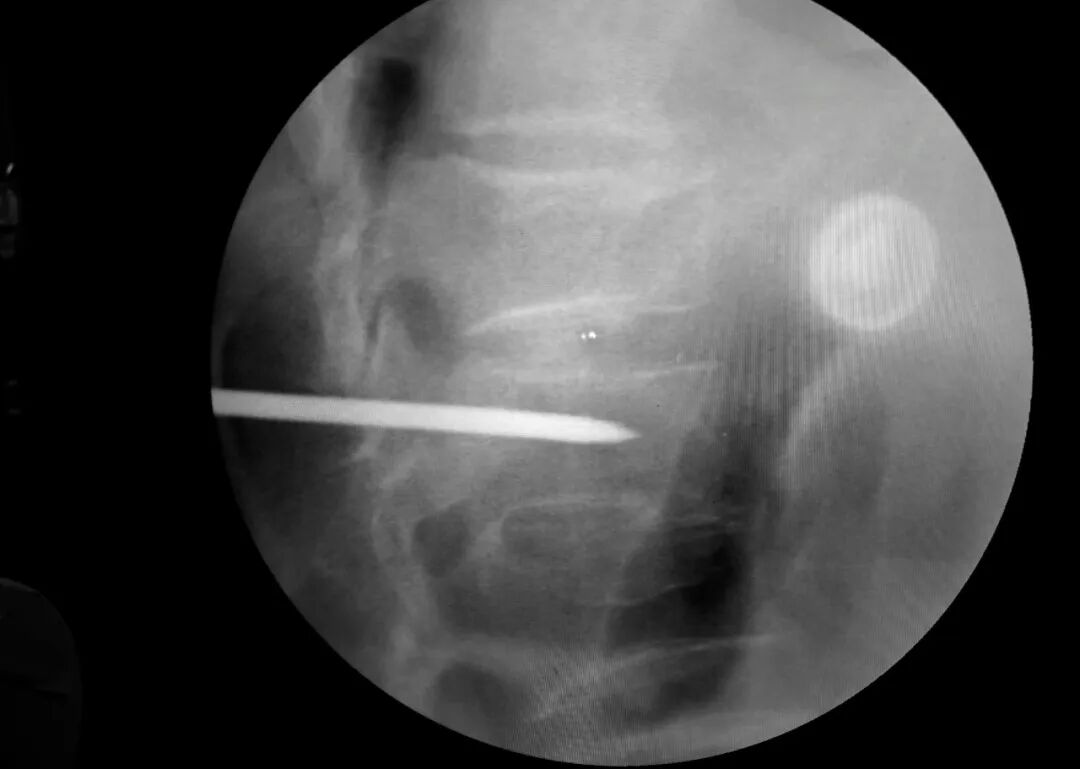

病例回顧 骨折部位 術(shù)中C臂協(xié)助定位 在C-臂監(jiān)視器透視下,分別定位胸12雙側(cè)椎弓根位置,標記穿刺點,僅以穿刺點為中心做3mm切開,在透視下注入骨水泥,再次透視見骨水泥位置良好。 骨水泥注入 術(shù)后影像學檢查 手術(shù)切口1cm左右 該手術(shù)經(jīng)皮透視下穿刺,手術(shù)切口小,創(chuàng)傷小,無需縫合,術(shù)后患者即感腰部疼痛明顯減輕,第二天可下床行走,已無腰痛不適,張大娘非常高興,自己再也不會受腰痛折磨整日與床為伴了。 我院脊柱骨科近年來,已成功開展多臺PVP手術(shù),為廣大老年患者減輕了病痛,減少了患者臥床時間,提高了生活質(zhì)量,是骨質(zhì)疏松性椎體骨折患者的福音。如果家里的老人突然出現(xiàn)了腰背疼痛,翻身下床困難,或者出現(xiàn)了腹部不適,排除腹部疾病(因為很多胸腰椎骨折患者在早期以腹痛腹脹為最主要癥狀),無論有沒有外傷史,建議帶老人及早就醫(yī),如果發(fā)現(xiàn)椎體損傷,積極治療,讓老人度過一個輕松愉快的晚年生活。 科普小講堂:經(jīng)皮椎體成形術(shù) 什么是骨質(zhì)疏松性椎體骨折? 骨質(zhì)疏松性椎體壓縮骨折,即在日常生活中患者并未遭受到明顯的外力而發(fā)生的骨折。這種骨折與創(chuàng)傷性的骨折不同,是由于自身骨質(zhì)疏松所導(dǎo)致的骨組織病變。骨質(zhì)疏松性骨折發(fā)生時,患者會感覺到背部明顯疼痛,翻身或起床等動作會讓疼痛更加明顯。 骨質(zhì)疏松性椎體壓縮骨折的危害有哪些? 一旦椎體發(fā)生骨質(zhì)疏松性椎體壓縮骨折,常常會導(dǎo)致患者出現(xiàn)腰背部持續(xù)性疼痛、季肋部放射痛、后凸畸形、呼吸功能受限及胃腸道癥狀等諸多癥狀,造成老年患者生活質(zhì)量下降。 什么是經(jīng)皮椎體成形術(shù)? (Percutaneousvertebroplasty,PVP)是一種新型的脊柱微創(chuàng)手術(shù),通過采用經(jīng)皮穿刺的方法,經(jīng)過椎弓根或是直接向椎體中注入骨水泥,使得椎體的強度和穩(wěn)定性得以提升,防止塌陷,從而達到緩解腰背疼痛,甚至部分恢復(fù)椎體高度的目的。 PVP手術(shù)優(yōu)點是什么? 1.恢復(fù)顯著:通常術(shù)后6個小時即能達到穩(wěn)定固定,患者可下床站立活動,大大縮短了患者臥床的時間。 2.疼痛減輕:術(shù)后患者會發(fā)現(xiàn)腰背部疼痛明顯減輕。 3.微創(chuàng):該治療方法僅需在皮膚上留2-3mm的穿刺針孔。 4.安全性:由于手術(shù)采用的是局部麻醉,因此即便是存在多種基礎(chǔ)病的患者也能夠耐受手術(shù),整個手術(shù)過程相對安全。 就診地址 酒泉市中醫(yī)醫(yī)院四樓脊柱骨科 咨詢電話 一樓門診部:0937-2669161 王醫(yī)生:13209409826 ??? 張醫(yī)生:18219971722